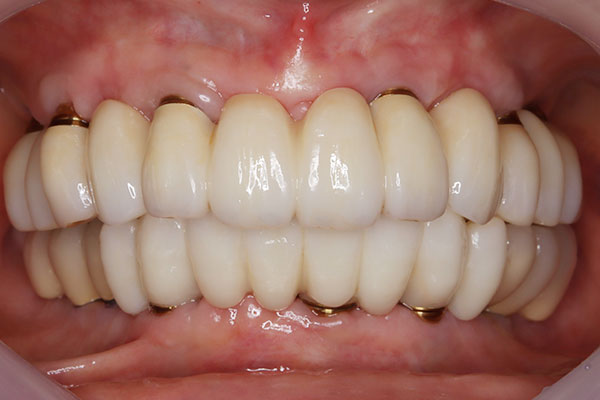

• 治療前

• 治療後

上顎6本、下顎6本。¥6,259,000

多くの歯に重度の虫歯や歯周病がみられたケース。歯周病の治療を行いAIl-on-6による包括治療を行った。